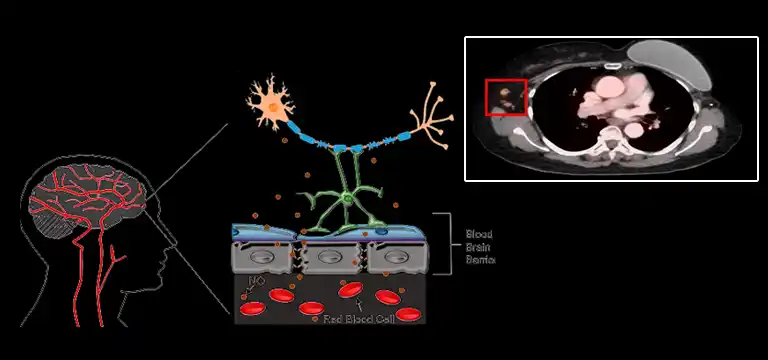

The principle behind detection of tumor cells in body by using PET scan is detection of radioactivity emitted by the radio tracer in the body.

Radiotracer is glucose which is radio – labeled and it is injected into the body 1-2 hours before the actual scanning and imaging part of PET scan takes place.

Tumor cells are metabolically more active as compared to non-cancerous cells. Hence, they exhibit hypermetabolism or hypermetabolic activity.

As a result of hypermetabolism, cancerous cells take up much more glucose as compared to non-cancerous cells.

Radiotracer that is injected into the body before scan has radio-labeled glucose. The radioactivity is detected as it emits photons.

Cancerous cells take up more radio-labeled glucose (FDG - fluorodeoxyglucose) because of hypermetabolism and appear different in color as compared to non-cancerous cells.

The color intensity and difference in colors that appear during PET scan signify different levels of metabolic activity of tissues.

Usually, cancerous cells have high metabolic activity. It is also referred as high glycolytic activity as these cells (tumor cells) take up FDG in much more amounts as compared to normal/ non-cancerous cells.

The color coding in PET scan helps in visual interpretation of low, moderate and high uptake of FDG by tissues in the body.

Blue-green colors show moderate to low metabolic activity, yellow-orange colors indicate high metabolic activity and red indicates very high and alarming metabolic activity.

PET scan is more accurate than any standard approach in detecting metastasis of cancer. PET scan is unable to detect small microscopic tumors but it is efficient in detecting clusters of cells (tissues) that spread to other organs of the body.